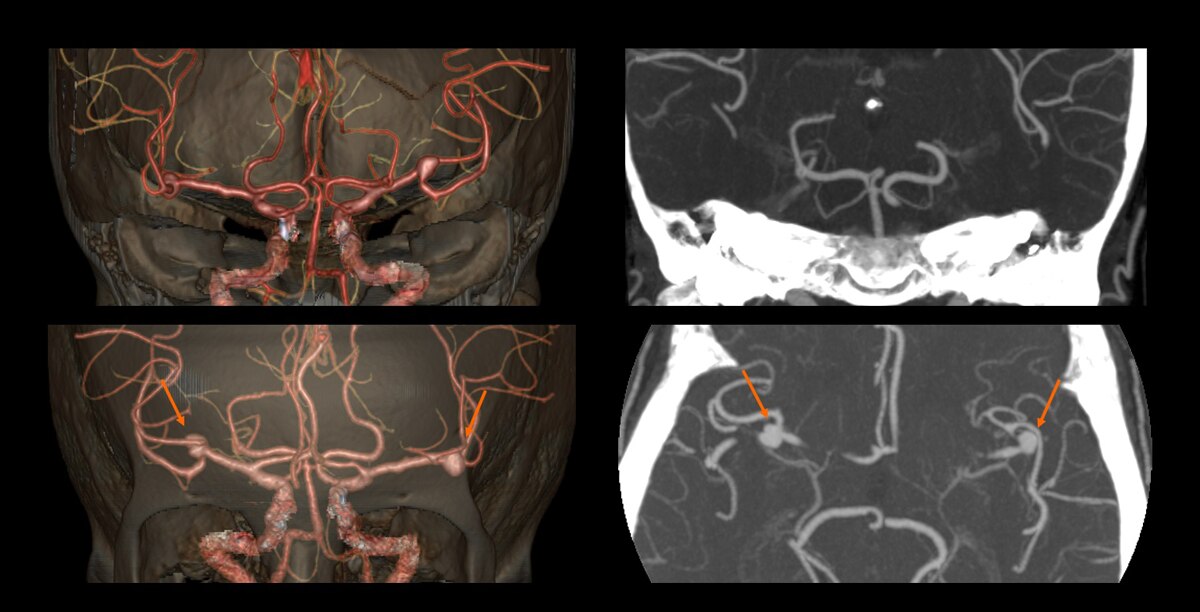

Carotids, assessment of aneurism at 1.8 mSv1